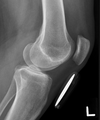

what is the most important thing to line up on a lateral knee

articulating surfaces of femoral condyles

the medial tibial plateau is __ the lateral tibial plateau is __

medial curved lateral straight

correction

more cephalad angle more external rotation

more internal lrotation less cephalad angle